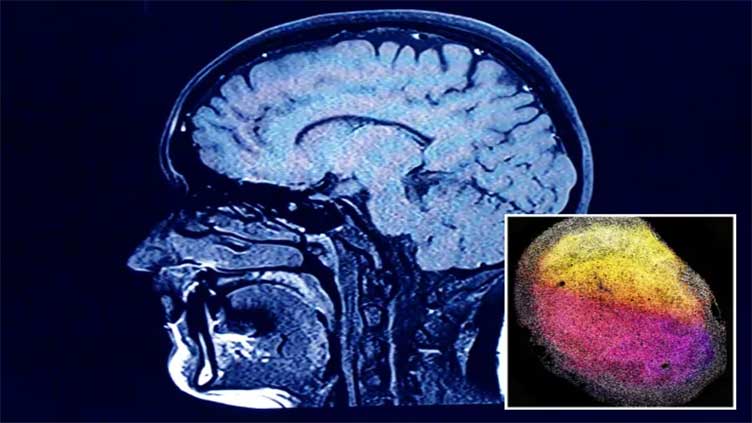

(Web Desk) - Scientists have developed lab-grown “minibrains” from human foetal brain tissue for the first time.

The tiny organoids — the size of a grain of rice — mimic how full-size brains work, offering “exciting” possibilities for new treatments, Dutch researchers said.

The latest development, published in Cell, saw brain organoids developed from human tissues in a world first.

Researchers used small pieces of foetal brain tissue — grown in the womb — to build the miniorgans.

They found the pieces of foetal brain tissue was able to “self organise” into organoids.

The organoids kept characteristics from the part of the brain from which the tissue came from.